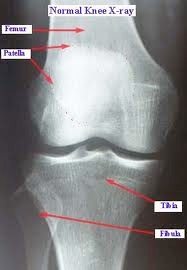

The x-ray above shows reduced joint space between the tibia and the femur in the medial tibio-femoral compartment.

WHAT DOES THE X-RAY SHOW?

When a surgeon looks at your x-rays he is looking for reduced joint space (thinning of the cartilage covering), extra new bone formation (osteophytes), bone cyst formation and thickening of the bone underneath the joint surface (subchondral sclerosis). These are all radiological signs of osteoarthritis. He will also be looking at the quality of your bone, the alignment of your leg and for any evidence of bone loss in severe deformities.